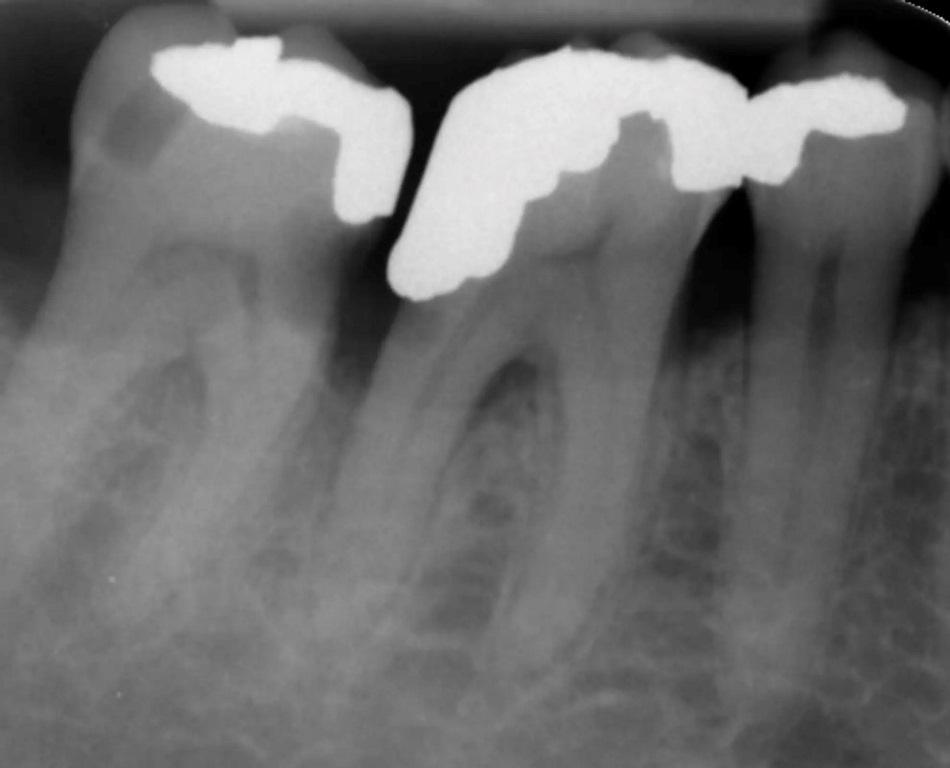

57-летний мужчина обратился в клинику с жалобами на разрушение двух коренных зубов, 46 и 47. У пациента не было патологий в анамнезе, оба коренных зуба имели обширный кариес и поврежденные пломбы (фото 1–6).